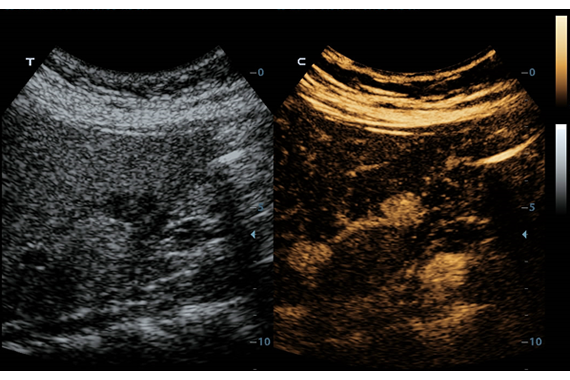

• PSH™ - технология гармонической визуализации с фазовой инверсией.

• iBeam™ - режим многолучевого компаундинга.

• iClear™ - адаптивный режим шумоподавления.

Эластография:

Компрессионная, Сдвиговая

Эластография сдвиговой волной/Эластометрия:

Да

Компрессионная эластография: